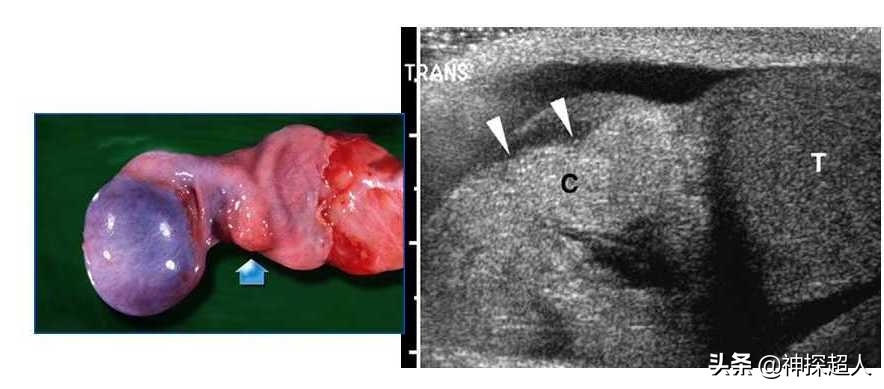

超声检查过程中的体格检查:患者右侧阴囊稍肿大,外部皮肤无红肿、破溃,触摸*丸睾**质地较硬,轻触痛。

超声检查提示:*丸睾**肿胀近似球形,回声减低,CDFI于*丸睾**内未探及血流信号。

术中探查:左侧*丸睾**呈紫黑色,精索与*丸睾**连接部粘连明显,呈360度扭转,将*丸睾**精索复位,温盐水纱布湿敷,观察10分钟颜色无变化,切开*丸睾**可见暗黑色血性液流出,无活动性出血,考虑*丸睾**完全坏死。